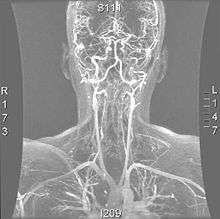

A reconstruction of the vertebral arteries from a CT scan, seen from the front. From the bottom, V1 is from the subclavian artery to the foramina, V2 is from the foramina to the second vertebra, V3 is between the foramina until entry into the skull, and V4 is inside the skull embedded in the dura mater. They merge into the basilar artery, which then divides into the posterior cerebral artery.

The vertebral arteries arise from the subclavian artery, and run through the transverse foramen of the upper six vertebrae of the neck. After exiting at the level of the first cervical vertebra, its course changes from vertical to horizontal, and then enters the skull through the foramen magnum. Inside the skull, the arteries merge to form the basilar artery, which joins the circle of Willis. In total, three quarters of the artery are outside the skull; it has a high mobility in this area due to rotational movement in the neck and is therefore vulnerable to trauma. Most dissections happen at the level of the first and second vertebrae. The vertebral artery supplies a number of vital structures in the posterior cranial fossa, such as the brainstem, the cerebellum and the occipital lobes. The brainstem harbors a number of vital functions (such as respiration) and controls the nerves of the face and neck. The cerebellum is part of the diffuse system that coordinates movement. Finally, the occipital lobes participate in the sense of vision.[1]

Magnetic resonance angiogram of the neck vessels in a person with Ehlers-Danlos syndrome type IV; it shows a dissection of the left internal carotid artery, dissection of both vertebral arteries in their V1 and V2 segments and a dissection of the middle and distal third of the right subclavian artery. Such striking episodes of dissection are typical for this "vascular" subtype of Ehlers-Danlos syndrome.